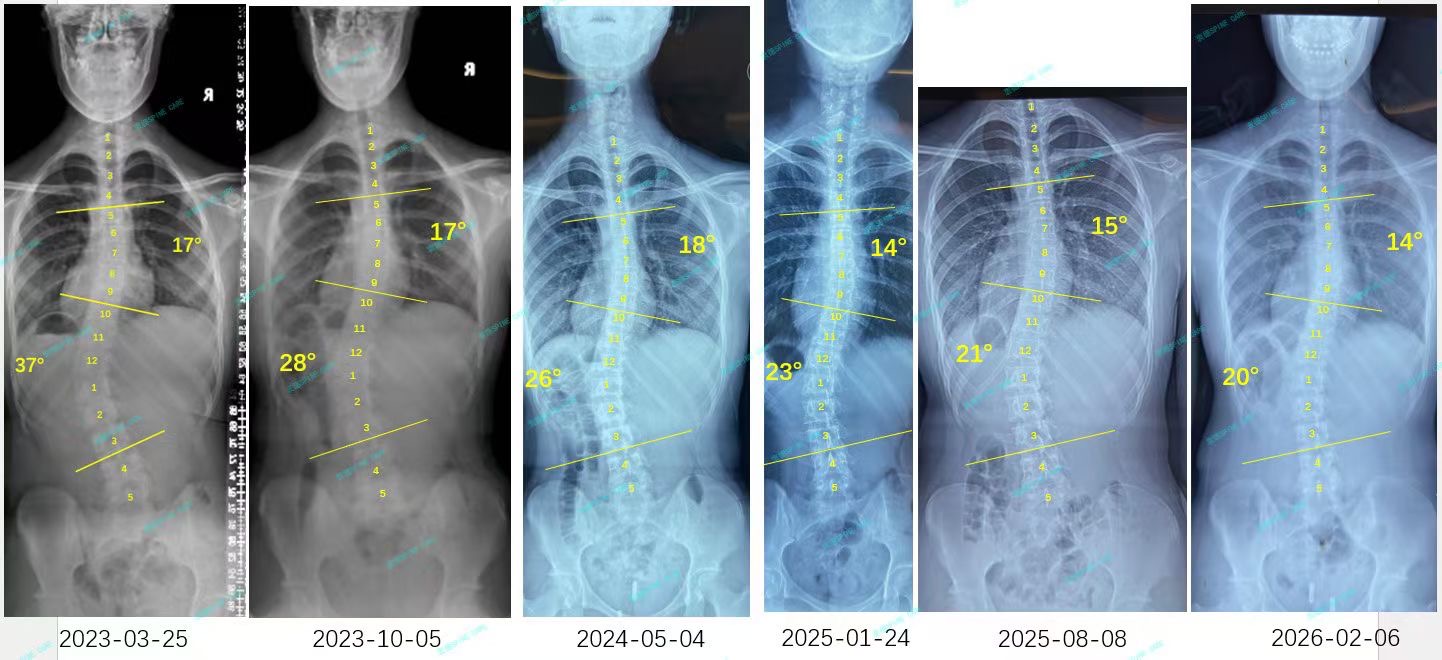

我是小欣,今年15岁,一次普通的校园体检,让我第一次听到了"脊柱侧弯"这个词。X光片上那道刺眼的曲线显示:腰弯37度,胸弯17度。镜子前,我清楚地看见自己扭曲的肩膀和歪斜的骨盆,连最简单的站立都变得不再自然,心里满是自卑与无助。

I'm Xiaoxin, and I'm 15 years old. During a routine school physical examination, I first encountered the term "scoliosis." The glaring curve on the X-ray revealed that my lumbar spine was at a 37-degree angle, while my thoracic spine was at a 17-degree angle. In front of the mirror, I could clearly see the distorted shoulders and tilted pelvis, and even the simplest act of standing became unnatural, leaving me with feelings of inferiority and helplessness.

结果出来,腰弯从37度降到20度,胸弯从17度降到14度,腰椎旋转也降到4度!看着片子上变化,泪水一下涌出来,这三年的汗水没白流。那张对比X光片,记录的不只是角度的变化,更是一个少女重获自信的历程。

The results showed that the curvature of the waist had decreased from 37 degrees to 20 degrees, the curvature of the chest had decreased from 17 degrees to 14 degrees, and the rotation of the lumbar spine had also decreased to within 5 degrees!As I looked at the changes on the X-ray, tears welled up in my eyes; all the hard work over the past three years had not been in vain. That X-ray comparison not only documented the changes in the angles but also the journey of a young girl regaining her confidence.